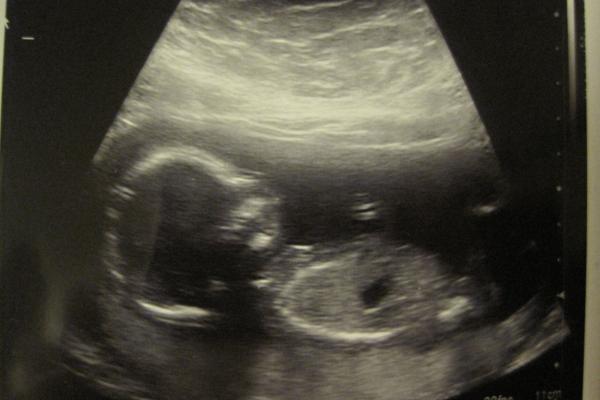

Efter RUL förra veckan börjar man så sakteliga förstå att det finns ytterligare ett mirakel på jäsning inför livet i denna värld. Även denna graviditet är känslan av förundran lika stor!